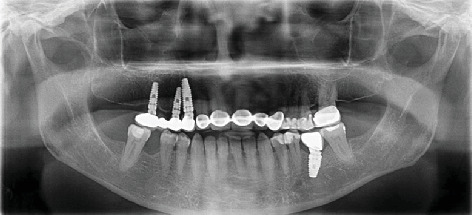

前言:种植牙科作为治疗缺牙患者康复的首选,其需求日益增长。临床医生可以在无牙空间遇到无症状的保留根碎片。本病例报告介绍了种植体晚期失败的长期预后,种植体放置11年后仍有根残余附着在固定装置上。病例报告:一名68岁女性患者在首次植入种植体11年后,因上颌右侧四单元种植体支撑桥功能相关而就诊。拔除修复体后,发现残根附着在中间支撑种植体的固定物上。种植体无意中侵占了残根碎片的中间部分,这是在拔桥时意外发现的。结论:考虑到潜在的阻碍骨整合的风险,临床医生在种植体中使用保留的根残余物时应格外注意。然而,被侵占的种植体和根碎片的骨整合是合理的,没有观察到有害的短期影响。风险-收益评估应该单独评估,因为后期失败仍然可能发生。试验注册:ClinicalTrials.gov标识符:NCT06671678。

Introduction: There is a growing demand for implant dentistry as the first choice of rehabilitation for treating patients with missing teeth. Clinicians can encounter asymptomatic retained root fragments in edentulous spaces. This case report presents the long-term prognosis of an implant resulting in late failure, with an attached root remnant to the fixture 11 years after implant placement. Case Report: A 68-year-old female patient presented to the clinic with complaints of function related to a maxillary right four-unit implant-supported bridge 11 years after the first insertion of the implants. After the removal of the restoration, a root remnant was found as adhered to the fixture of the middle supporting implant. The implant was placed encroaching upon the mesial part of the residual root fragment left unintentionally, which was discovered accidentally during the bridge removal. Conclusion: Clinicians should show ultimate attention when utilizing the retained root remnants in implant sites, considering the potential risk of hindering osseointegration. However, osseointegration of the encroached implant and root fragment is plausible, with no detrimental short-term impacts observed. A risk-benefit evaluation should be assessed individually, as late failures can still occur. Trial Registration: ClinicalTrials.gov identifier: NCT06671678.